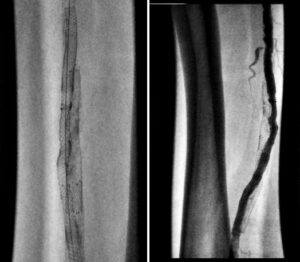

Figure 1. Occluded stent with wire crossing outside the stent

Figure 2. Gradual balloon dilation upsizing from 4-6 mm diameter outside the stent

Figure 3. Angiographic results post stent deployment in the subintimal space.

Access was gained in the left common femoral artery. We advanced a 7-frech Pinnacle 65cm sheath up and over to the right CFA. We were able to probe the vessel outside the previously occluded stent and gain access to the true lumen of the vessel beyond the occluded stent in the distal right SFA. A number of wires were used, including stiff Glidewire and an Amplatz wire. The stiff straight guidewire was used, along with a vertebral catheter, QuickCross catheter, and Trailblazer 0.035 catheter. We dilated the vessels with a 3.5mm Nanocross balloon. We then dilated the right superficial femoral artery with a 6mm balloon, followed by a 7mm balloon. After dilation, right SFA occlusion went from 100% to 60% severe recoil. We deployed 6×120 and 6×80 Supera stents, overlapping them with care to improve stacking of the stents to optimize radial strength. This was in the mid to distal SFA. The completion angiogram revealed a good result, with less than 20% residual stenosis at the SFA post double-barrel stenting. Patient tolerated the procedure well and was kept on DAPT.